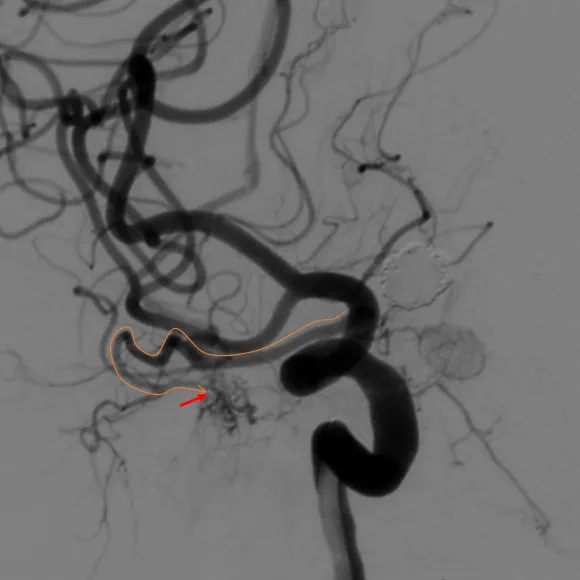

右颈内造影

经右眼动脉入路工作角度

经右眼动脉工作路径

SONIC微导管路径

SONIC微导管到位后手推造影确认

SONIC微导管到位较深,注胶时可采用楔入技术,Onyx胶基本未反流,头端无粘管, SONIC微导管头端未解脱即顺利拔管